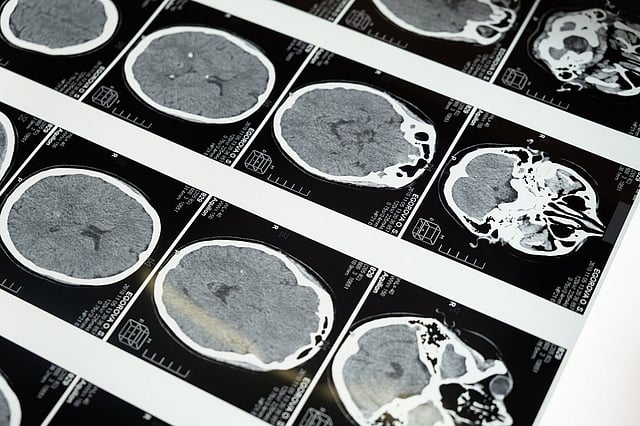

If a doctor feels that a patient has a brain tumour based on the symptoms listed above, they may offer diagnostic testing to confirm this. Neurological examinations are performed to assess the patient’s hearing, balance, vision, and reflexes, among other things, because issues in these areas may indicate that a specific portion of the brain is impacted by a tumour. To diagnose a brain tumour, imaging procedures such as Magnetic Resonance Imaging (MRI), Computerised Tomography (CT) scan, and Positron Emission Tomography (PET) scan are performed.